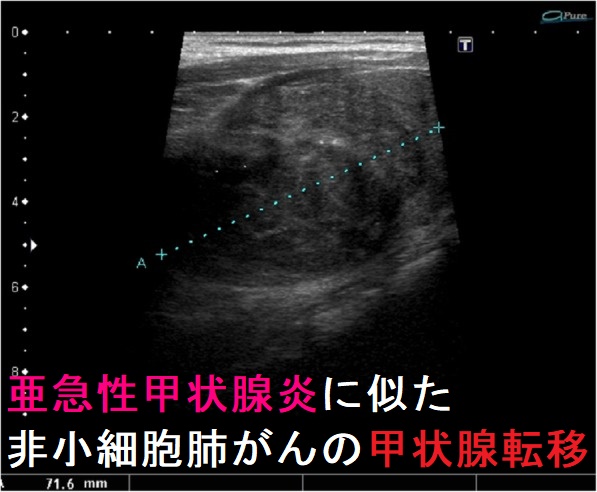

転移性甲状腺癌(他臓器癌から甲状腺へ転移)は①乳癌②肺癌(最多)③腎臓癌(臨床的に最も問題)④悪性黒色腫⑤胃がん・大腸がん・食道がんなど。超音波エコー検査で①低エコー領域②腺腫様甲状腺腫・良性濾胞腺腫・甲状腺濾胞癌と見分け付かず。癌性リンパ管炎をおこすと急激な前頚部腫脹、びまん性甲状腺腫、圧痛、破壊性甲状腺炎(甲状腺中毒症)、エコーで①びまん性低エコー像②樹枝状低エコー(拡張したリンパ管)③甲状腺腫大のみでSOL・低エコーを形成せず亜急性甲状腺炎・急性化膿性甲状腺炎と鑑別要。穿刺細胞診で低分化癌、未分化癌と判定され簡単に診断可能。

甲状腺に転移して癌性リンパ管炎をおこすと、

- びまん性甲状腺腫(甲状腺全体が腫れます)[急激な甲状腺びまん性腫脹(急性反応、急性一過性甲状腺腫大)と同じような超音波(エコー)所見。下記5.];〃。

- 甲状腺超音波検査(エコー)にて、

①びまん性低エコー像(腫瘤形成せず)

②樹枝状低エコー(拡張したリンパ管)

③甲状腺腫大のみでSOL・低エコーを形成しない事がある;亜急性甲状腺炎・急性化膿性甲状腺炎と鑑別要。意外と穿刺細胞診で簡単に診断できます(下記6.)。

超音波(エコー)検査では、甲状腺全体がびまん性に腫大し、内部は低エコーまたは等エコーで不均一。低エコー線(樹枝状低rコー)を伴い網状パターン(癌性リンパ管炎)。[J Korean Med Sci. 2014 Jun;29(6):818-24.]